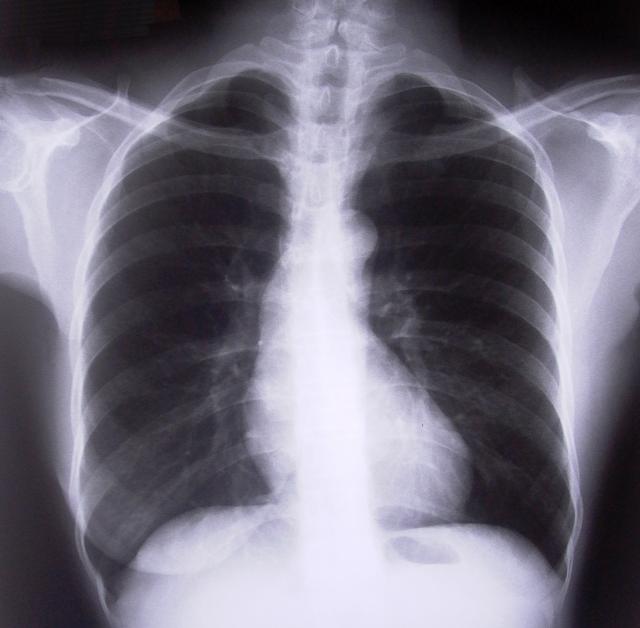

Gruźlica - choroba XIX wieku - niestety wciąż ma się dobrze, a jej przypadki nie są wcale jednostkowe. Tak wynika z danych ostrowskiego Sanepidu. W ubiegłym roku zanotowano ich 8 i jak twierdzą fachowcy, to o 8 za dużo. Choroba jest groźna i może prowadzić do śmierci, zwłaszcza że niektóre szczepy są wyjątkowo lekooporne.

"Kiedyś to była choroba wynikająca ze złych warunków życia, dotykająca najczęściej ludzi z marginesu społecznego" - powiedział Radiu Centrum dyrektor ostrowskiego Sanepidu Andrzej Biliński: